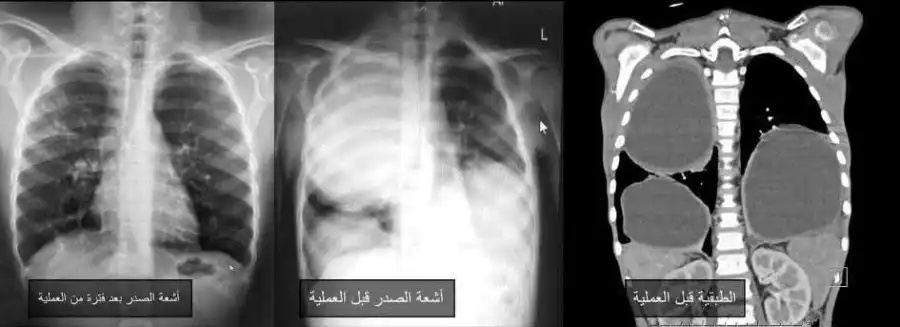

مدار الساعة -تمكن فريق جراحة الأطفال في مستشفى الجامعة الأردنية من علاج حالة نادرة لطفل يبلغ من العمر 9 سنوات، كان يعاني من "أكياس كلابية" ضخمة في كلتا الرئتين، عبر تدخلات جراحية دقيقة باستخدام المنظار الصدري، في إنجاز يعد من الحالات القليلة المسجلة طبيا.

وبحسب بيان المستشفى، اليوم الأحد، تكمن ندرة الحالة في أن "الأكياس الكلابية" تصيب الكبد غالبا، وقد تنتقل لاحقا إلى الرئتين، بينما تعد إصابة الرئتين فقط، وبشكل متعدد وضخم في الجهتين، من الحالات النادرة جدا، وقد جرى اكتشاف الحالة دون أعراض واضحة من قبل استشاري أمراض التنفسية والصدرية لدى الأطفال، الدكتورة إيناس الزيادنة، وفريقها الطبي.ونظرا لتعقيد الحالة وصعوبتها التخديرية والجراحية، تولى فريق التخدير بقيادة استشاري تخدير الأطفال الدكتور عمر عبابنة تقديم عناية تخديرية متقدمة، مكنت من إجراء عمليتين جراحيتين كبيرتين ومتتاليتين بأمان، فيما أجرى فريق جراحة الأطفال برئاسة استشاري جراحة الأطفال بالمنظار الدكتور رائد الطاهر العمليتين بنجاح كامل ودون مضاعفات، باستخدام المنظار الصدري بدلا من فتح الصدر الجراحي التقليدي.وأوضح الطاهر أن جراحات الأطفال بالمنظار تعد من أدق الجراحات ولا تجرى إلا في مراكز محدودة تمتلك التجهيزات والخبرات المتخصصة، مشيرا إلى أن مستشفى الجامعة الأردنية كان من أوائل المؤسسات المحلية التي تبنت هذا النوع من الجراحات المتقدمة للأطفال خلال السنوات الأخيرة.وساهم استخدام المنظار والثقوب الجراحية الصغيرة في تسريع تعافي الطفل بعد العملية الأولى للرئة اليمنى، ما أتاح إجراء العملية الثانية للرئة اليسرى بعد نحو أسبوعين فقط، وبنفس التقنية، وقد تعافى الطفل بشكل تام، وغادر المستشفى خلال مدة قياسية، مع متابعة طبية استمرت لعدة أشهر أكدت عودته لممارسة حياته الطبيعية دون أي مضاعفات.من جانبه، أكد المدير العام للمستشفى الدكتور نادر البصول حرص المستشفى على توفير أحدث التقنيات الجراحية والتخديرية ووسائل العناية الحثيثة، واستقطاب كفاءات طبية ذات خبرات عالمية وبعد أكاديمي متميز، بما يعزز مكانته كمركز طبي رائد يقدم خدمات صحية متقدمة على المستويين المحلي والإقليمي.